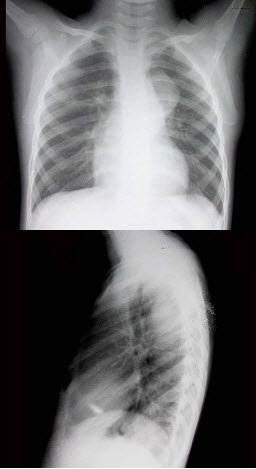

D.前列腺支架置入

男,1岁零8个月,生长发育差,易患呼吸道感染,心悸气促,心脏正、侧位片检查如图所示,正确的描述和诊断是()

A.正位示心影向两侧扩大,心尖左移

B.肺纹理增多

C.侧位示心前间隙变窄,心后食管前三角间隙消失

D.房间隔缺损

E.室间隔缺损